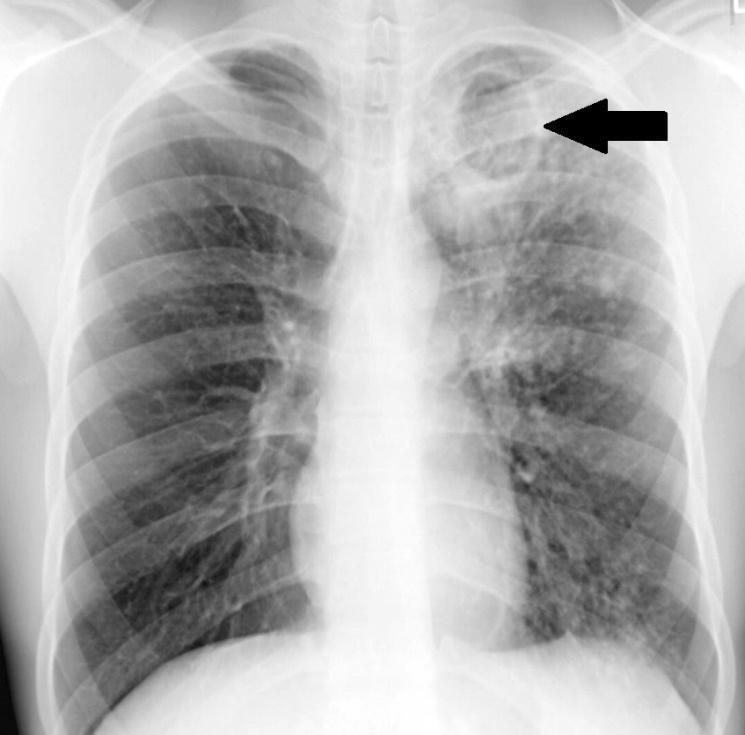

In afbeelding 1 is een röntgenfoto van een tbc-patiënt te zien. Met de pijl wordt een lymfeknoop aangewezen die is vergroot als gevolg van een tbc-infectie.